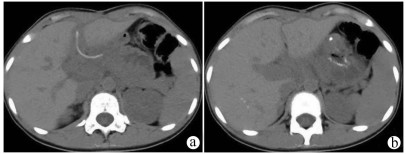

Surgical resection of liver metastases of ovarian cancer and the affected diaphragm and lung lobes via the intercostal approach: A case report

Daqun LIU, Ziyue WANG, Yushi CAO, Xing LYU, Guoyue LYU

2021, 37(11): 2649-2650. DOI: 10.3969/j.issn.1001-5256.2021.11.033

Abstract(741) HTML (437) PDF (2420KB)(42)

Abstract: